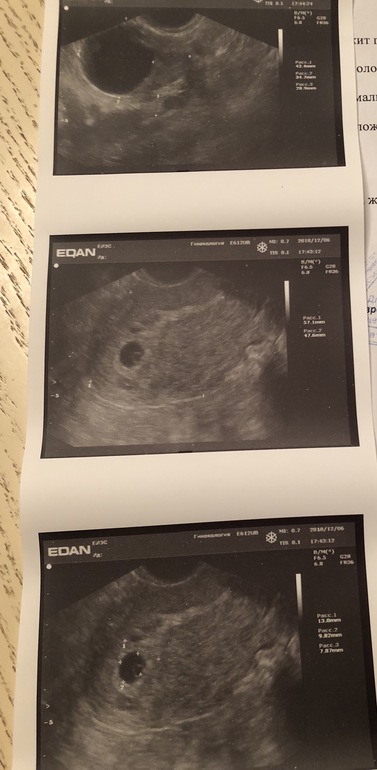

Теперь видно и на УЗИ

Результаты: УЗИ, КТГ, доплера, скринингапоследние М были 25.10. Увидев // сразу записалась на УЗИ, 27.11 ещё ничего не было видно,сказали сделать снова через 10 дней. Сегодня сходила, совсем крошечное плодное яйцо 9,82 на 7,87 мм. Я даже не понимаю какой это срок,врач был мужчина,сказал это 2-3 недели. Спросила когда будет биться сердце? Сказал через 2-3 недели.

Я в 3 недели делала узи, у меня плодное яйцо в диаметре было 8 мм и желточный мешок 2 мм

10 мм это не крошечное) вполне себе нормальное для 6 ак.недель.

И вроде ЖМ видно, или мне кажется?

Через 2 недели точно уже СБ должно быть слышно)

Поздравляю. Все отлично, хорошенькое ПЯ и уже жм видно. Через 2 недели услышате сб малыша